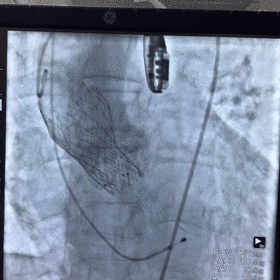

术中影像

图片

根部造影

球囊预扩

瓣膜释放至2/3造影观察

瓣膜释放后形态欠佳

经球囊后扩后瓣膜形态良好

手术结果

术后造影及超声探查未见瓣周漏,跨瓣压差术前183mmHg,术后几乎无压差,术中及术后未出现相关并发症,手术圆满完成。